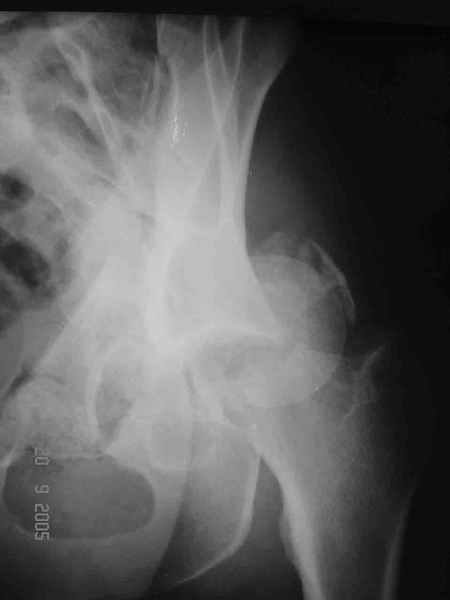

Больной 18 мая 2003 года в автоаварии получил перелом левой вертлужной впадины, вывих бедра. Госпитализирован в один из стационаров области.Вывих вправлен. В последствии бедро вывихивалось еще дважды. На консультацию был представлен снимок от 19.05.03г., больной переведен к нам 3.06.03г. Снимок при поступлении - перелом впадины, задне-верхний вывих бедра. 05.06.2003 г. выполнено открытое вправление вывиха левого бедра и остеосинтез стенки вертлужной впадины двумя винтами. Послеоперационный период без осложнений. Объем движений в левом тазобедренном суставе восстановился полностью. Выписан на амбулаторное лечение в удовлетворительном состоянии с рекомендациями 3 месяца ходить на костылях без нагрузки на оперированную конечность. На контрольных рентгенограммах левого тазобедренного сустава 13.10.2003 г. - признаки консолидации перелома; плотность, форма головки и состояние суставных поверхностей удовлетворительные. Разрешена дозированная осевая нагрузка, на конечность с использованием дополнительной опоры. 19.12.2003 г. больной обратился с жалобами на боли в левом тазобедренном суставе. На рентгенограммах левого тазобедренного сустава 19.12.2003 г., 20.02.04г. - асептичекий некроз головки бедра. 5.04.04г. - эндопротез. Сейчас ходит без трости, не хромает. Особенность эндопротезирования - при удалении винтов прослежена линия перелома заднего края впадины и предложено установить чашку несколько меньшего диаметра, чтобы она была покрыта несломанной частью.